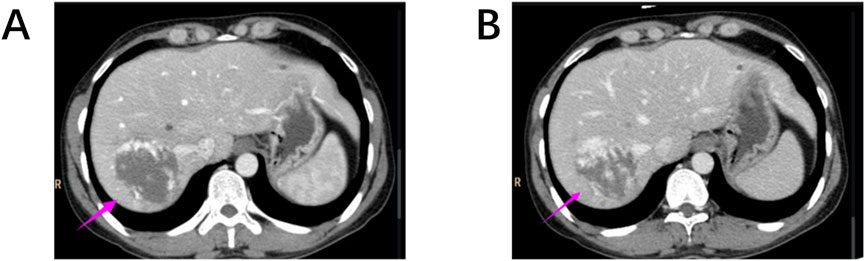

This enhancement pattern has not been reported in other renal tumors and aligns with our findings, suggesting it may be a distinctive imaging feature of RH. The “centripetal filling” phenomenon may be attributed to the tumor’s rich capillary network, which leads to cortical-phase CT values comparable to those of the adjacent aorta. Dynamic or multiphase scans reveal enhancement patterns resembling cavernous hemangiomas, likely due to slow intratumoral blood flow and prolonged contrast retention (Figures 4A,B). The heterogeneous enhancement could be related to recurrent intratumoral hemorrhage and fibrosis. However, due to the limited number of detailed imaging reports on RH, larger multicenter studies are required to validate these findings.

Figure 4. (A, B) Hepatic cavernous hemangiomas also exhibit a “centripetal filling” pattern similar to RH on contrast-enhanced CT scans.